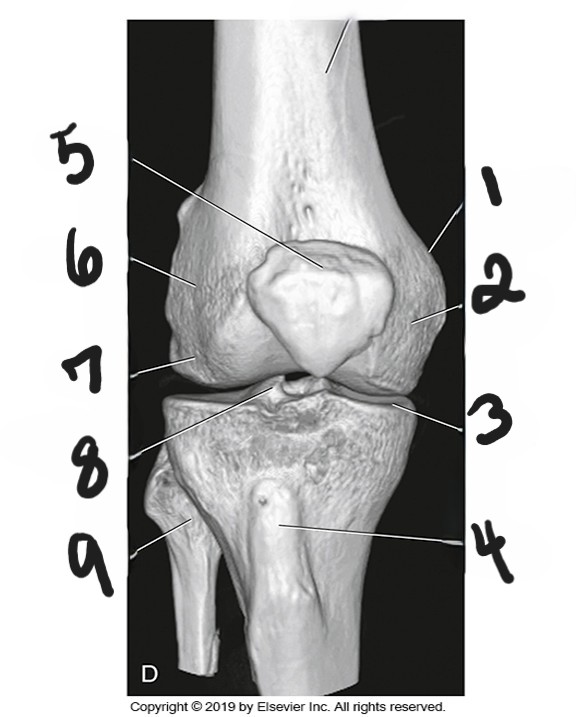

medial epicondyle

what is #1?

medial condyle

what is #2?

tibial plateau

what is #3?

tibial tuberosity

what is #4?

patella

what is #5?

lateral epicondyle

what is #6?

lateral condyle

what is #7?

intercondylar eminence

what is #8?

fibula

what is #9?